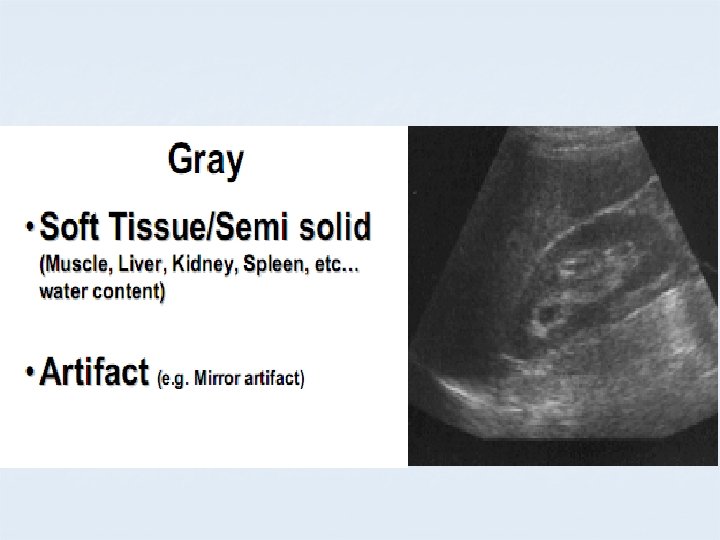

B MODE COLOURS BLACK ANECHOIC GREY HYPOECHOIC WHITE ECHOGENIC

APPEARANCE OF DIFFERENT TISSUES STRUCTURE APPEARANCE Viscera ; Liver Spleen Hypoechoic Muscles Hypoechoic with echogenic lines Blood, Urine, Bile, ascites, water Anechoic Bone, Stone Hyperechoic